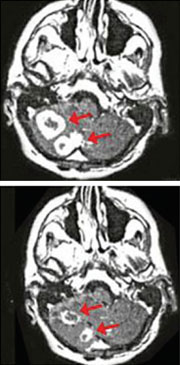

Improvement of brain cancer tumors 8 weeks following NexGen PDT